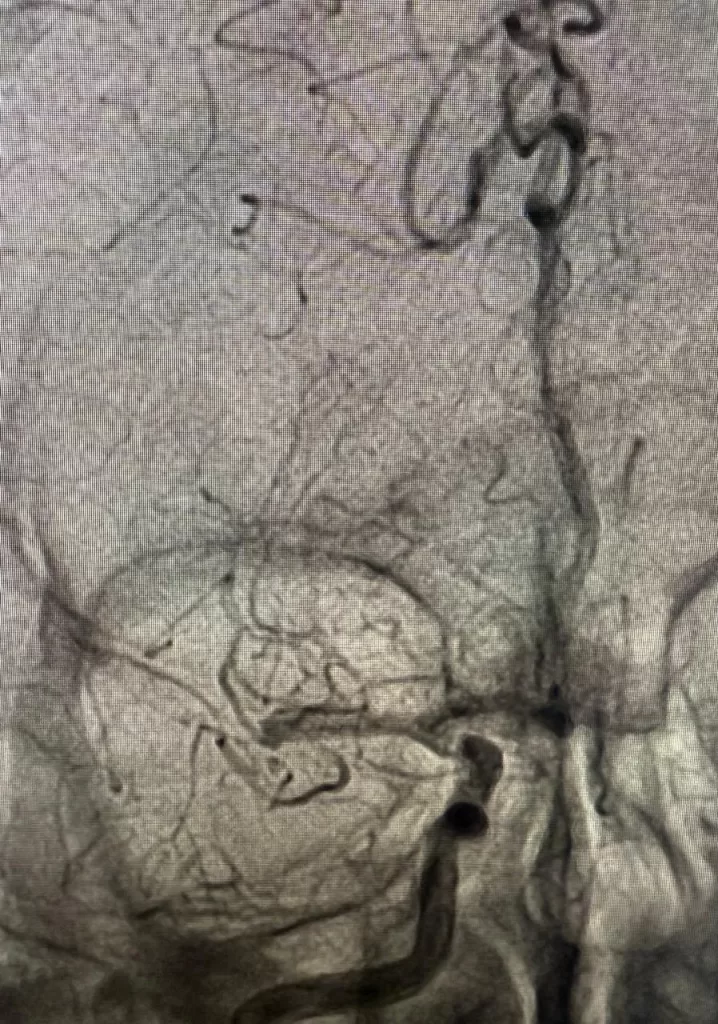

كما تم إجراء قسطرة مخية عاجلة لحالة أخرى لمريضة في الأربعينات من عمرها، محوَّلة من مستشفى السنبلاوين، كانت تعاني من نزيف تحت الأم العنكبوتية، وتبيّن بالفحوصات وجود تمدد شرياني بالشريان الأمامي المتصل.

وأُجري التدخل العلاجي تحت إشراف الأستاذ الدكتور أحمد عفت والدكتورة ندى عبد الحميد، وبما يتوافق مع أحدث البروتوكولات العلاجية المعتمدة.